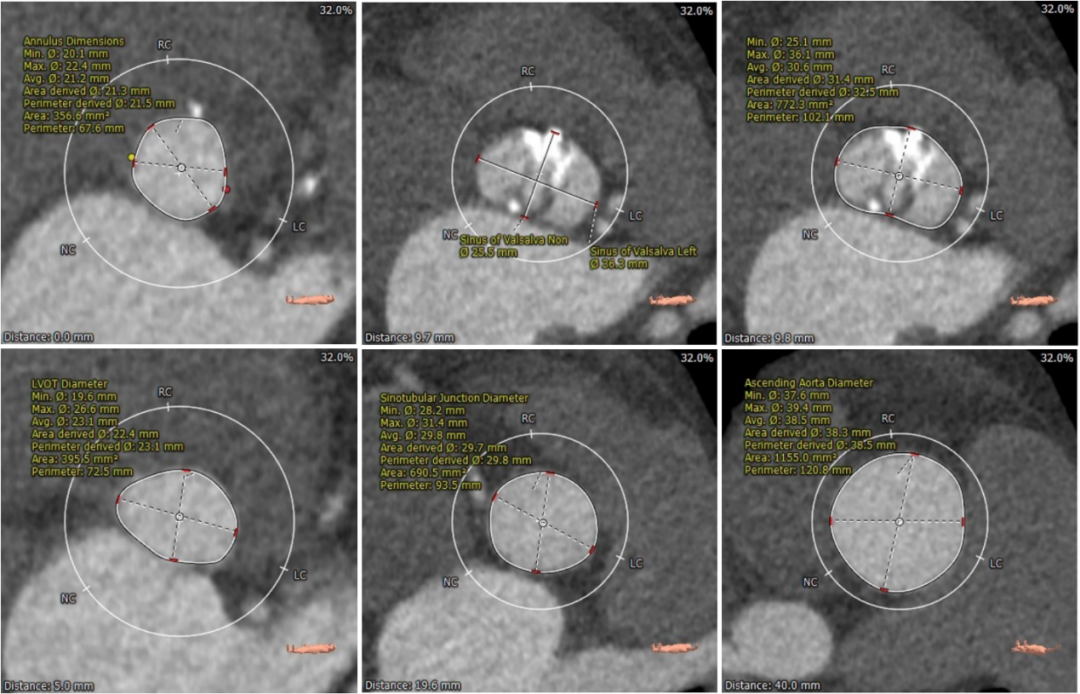

术前CT评估

Type0型二叶式主动脉瓣,重度钙化,钙化发布不均,位置靠右前侧,根据钙化形态预估,术中钙化推移难度较大,对人工瓣膜形态影响较大,存在人工瓣膜移位及瓣周漏风险。

左冠高度稍低,左冠起始处可见局限钙化,左冠瓣瓣叶长度偏长,综合瓦氏窦内径等因素考虑,左冠存在遮挡风险。

左室腔内径有增大,心室壁增厚。

入路血管多处钙化,腹主动脉分叉前病变较重,双侧血管内径良好,整体入路血管条件尚可。

主动脉根部测量

瓣上结构测量

冠脉阻挡风险及钙化评估

外周血管入路评估